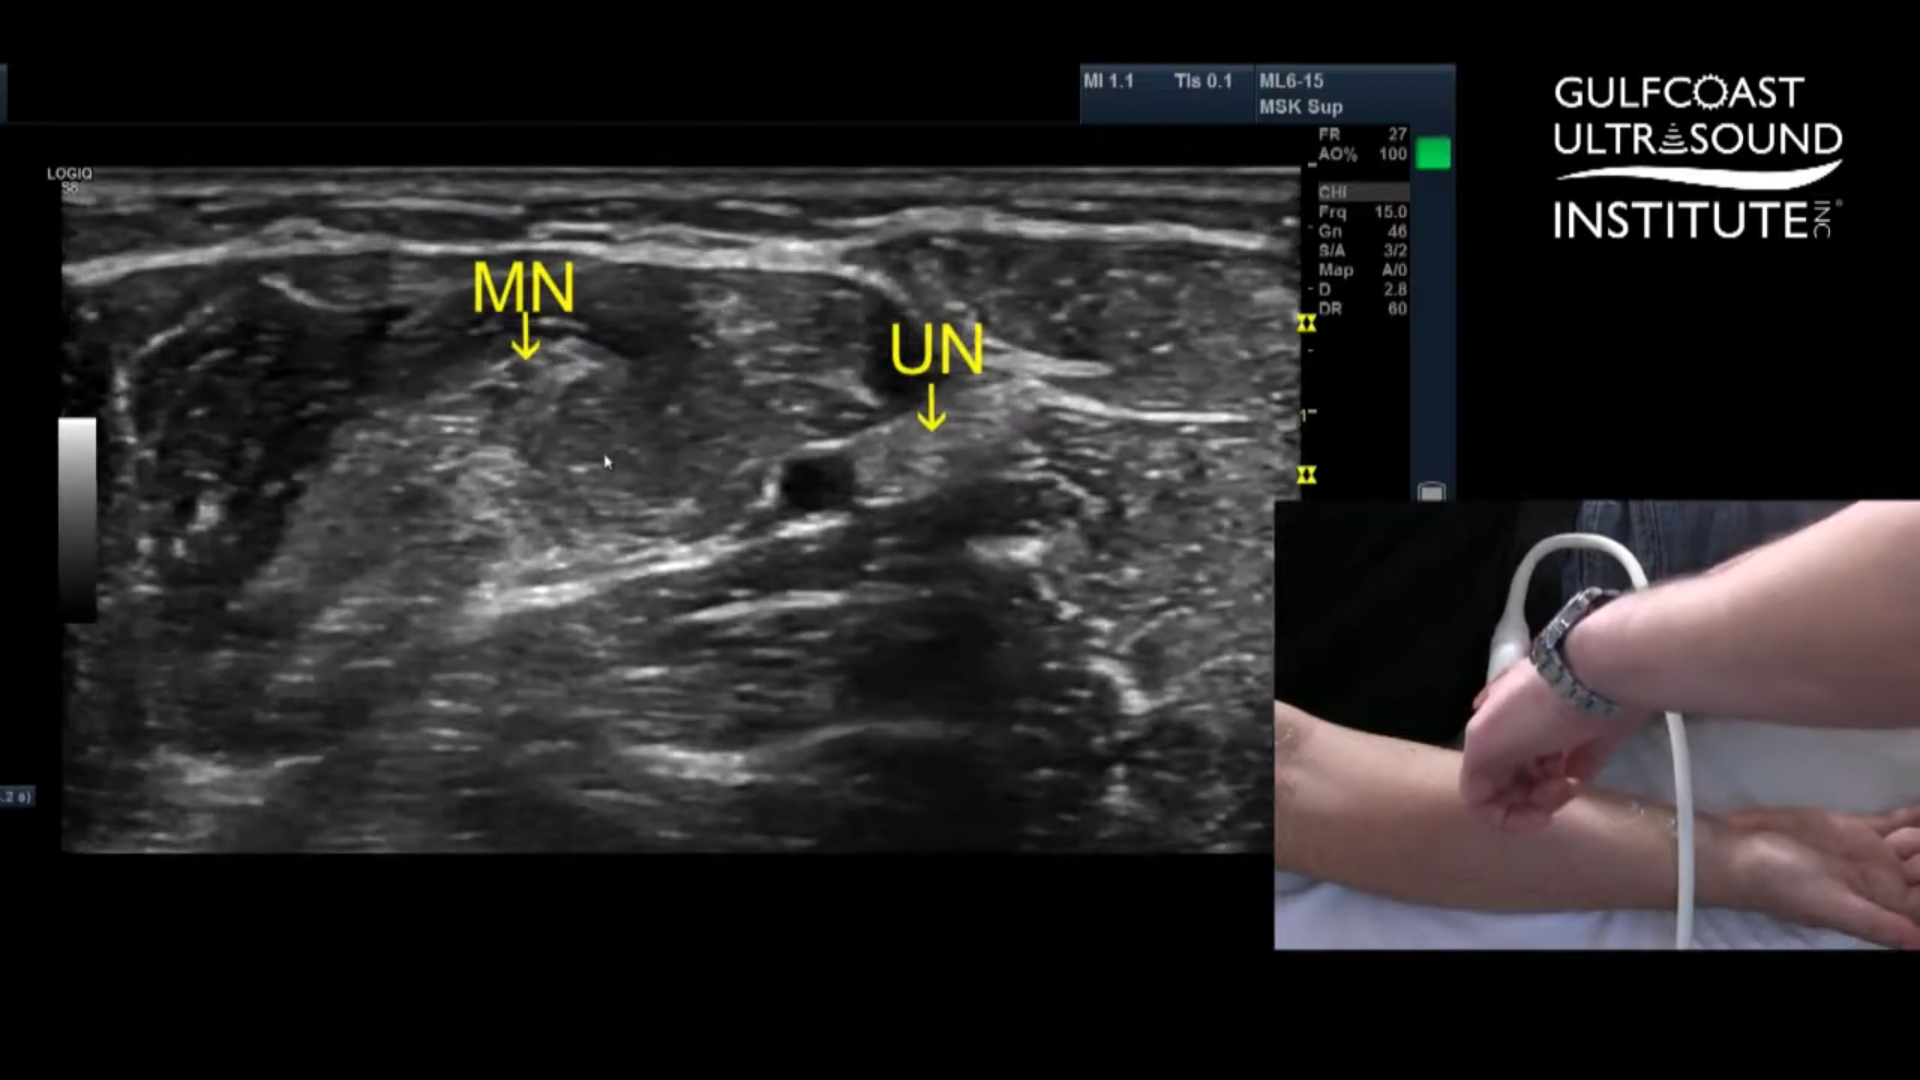

Identify the Median Nerve from the Same View

Once you're in that same mid-forearm area, glance medially. You’ll often spot the median nerve in that same imaging plane. With a bit of finesse, you can line up your probe to visualize both the ulnar and median nerves simultaneously. This is a huge advantage, because with one well-placed injection, you can block both nerves at once.